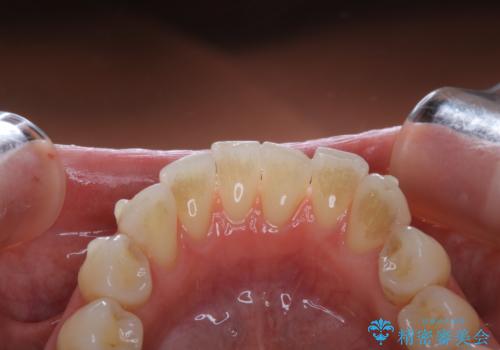

- インビザライン矯正治療中にステインが気になるとのことで来院されました。全体的にステインが付着していたため自費クリーニングPMTC(60分コース)を行いました。

インビザライン矯正治療中は、ご自身の歯にアタッチメントという突起物(効率的に歯の移動を行うため)をつけます。そのため、通常時よりもステインが付きやすい状態になることがあります。

インビザラインは透明なマウスピースなので、ご自身の歯にステインなどが付着していると、見た目に影響してしまうことがあります。

矯正治療中の虫歯・歯周病・口臭予防としても、定期的にPMTCを行うことが大切です。